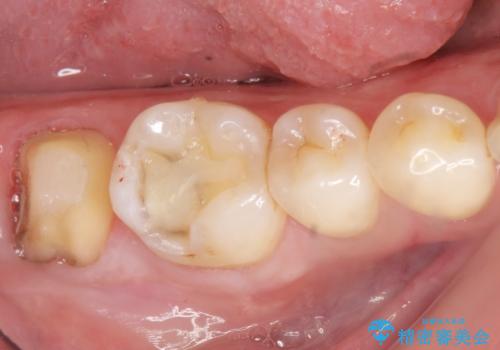

銀歯を除去し、歯周外科処置(右下7遠心の骨整形及びディスタルウェッジ)を行った後にメタルボンドクラウンによる補綴を行いました。

隣の歯(右下6)はセラミックインレーで修復しました。

歯周外科処置(右下7遠心の骨整形及びディスタルウェッジ)により、深部に及ぶう蝕を除去するとともに歯肉縁上の健全歯質を獲得でき、適合の良い被せ物を作製することができました。

不適合な銀の詰め物とう蝕の除去により奥歯の違和感がなくなり、セラミック治療により機能性・審美性が向上し、患者様に喜んで頂けました。

被せ物の種類:右下6 e-max press セラミックインレー

右下7 メタルボンドクラウン エコノミー